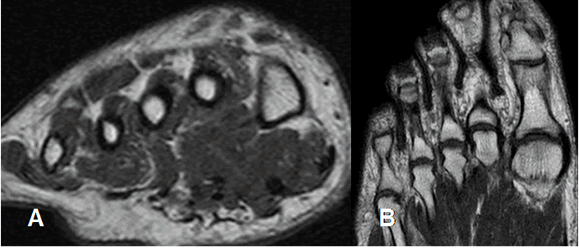

La Resonancia Magnética (RM) es el estudio de elección, para la valoración del tobillo y el pie. Permite estudiar las estructuras óseas y los tejidos blandos, que incluyen músculos y tendones, ligamentos, nervios, espacio articular, etc.

Las secuencias deben incluir cortes axiales, sagitales y coronales. En el tobillo los cortes se orientan en relación con la mesa de examen y en el pie, en relación con el eje longitudinal de los metatarsianos. (1). (Fig 6 y 7).

Fig 6. Orientación de los cortes en el tobillo.

A: RM axial y B: RM coronal.

Fig 7. Orientación de los cortes en el pie.

A: RM coronal y B: RM axial.